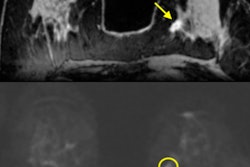

The mpMRI studies were performed on both 1.5-tesla and 3-tesla MRI scanners at several institutions. Sequences included T2-weighted, axial chemical shift T1-weighted, and dynamic contrast enhanced T1-weighted imaging. Because diffusion-weighted MR images were routinely acquired at UT Southwestern -- but not always at other facilities -- the researchers did not evaluate results using that sequence (Journal of Urology, October 2017, Vol. 198:4, pp. 780-786).

By setting a parameter score of 4 or greater for clear cell carcinoma, the researchers achieved sensitivity of 78% and specificity of 80%. With a score of 3 or greater, sensitivity increased to 95% but specificity slipped to 58%. Interobserver agreement was moderate to good with a mean of 0.53.